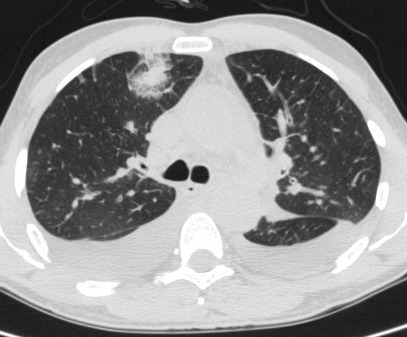

• puis une hyperéosinophilie sanguine et tissulaire, à l’origine d’opacités alvéolaires localisées non systématisées périphériques, uni- ou bilatérales, généralement à type d’infiltrats (fig. 12) ;